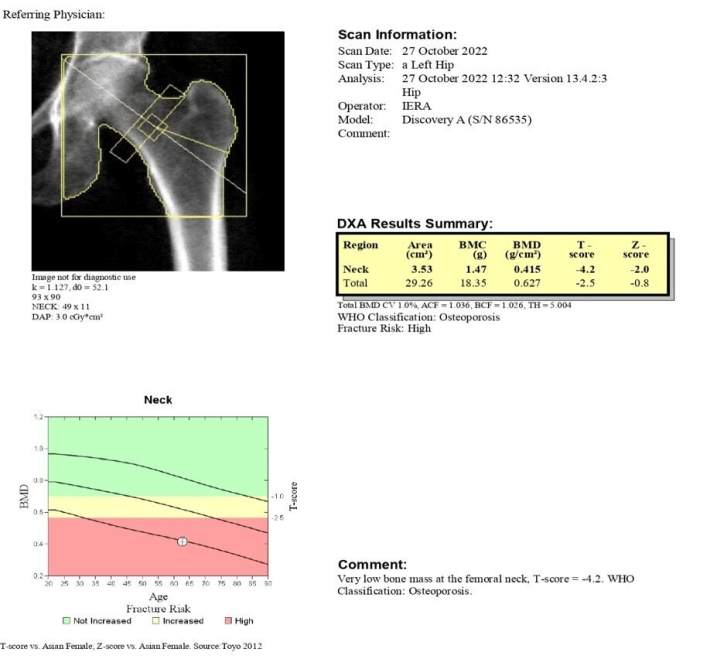

Left Hip Upon Admission

- 1st DXA scan done upon admission

2nd DXA scan done after 12 months of Romosozumab therapy

- Spine BMD changes: [(0.739-0.558)/0.558] X 100% = 32.4%

- Hip BMD changes: [(0.688 - 0.627)/ 0.627] X 100 = 9.7%